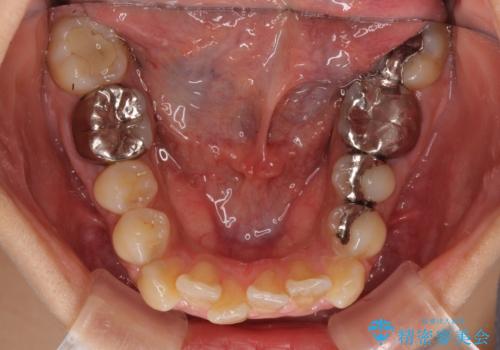

デコボコと口元の突出感 ハーフリンガルでの抜歯矯正

- 前歯のデコボコと上顎の前突感による口の閉じにくさを気にして来院された患者様です。

目立たない装置を希望されたので、上顎が裏側装置のハーフリンガルを選択し、上下左右の小臼歯(計4歯)を抜歯して矯正治療を行うこととしました。

表側のワイヤー矯正に比べると治療期間は長く、費用も高額となりますが、どうしても目立たせたくないという方にはお勧めの抜歯矯正です。